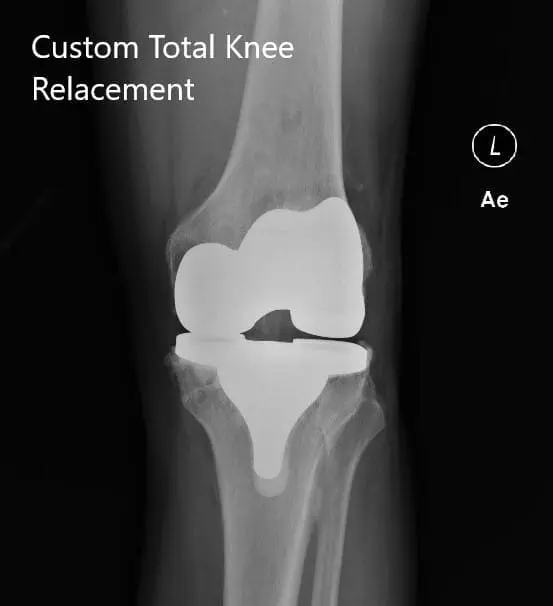

Postoperative X-ray of the left knee showing AP and lateral views

Postoperative X-ray of the left knee showing AP and lateral views - img 2

PROSTHESIS: Custom tibial tray with a custom femoral component with 6-mm polyethylene insert with a 32 -mm patella.